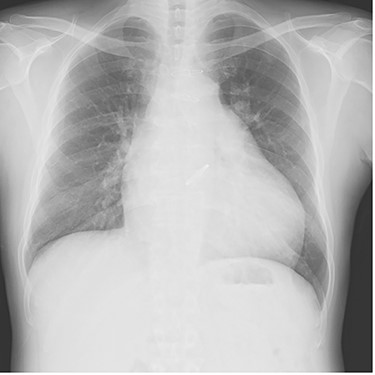

The patient was extubated on the third postoperative day. He was weaned off catecholamines on postoperative Day 9 and transferred from the intensive care unit on postoperative Day 10. Postoperative transthoracic echocardiography revealed no prosthetic valve dysfunction at either the aortic or pulmonary positions. Although his general condition was good, he had prolonged wound healing in the right inguinal region and resisted conservative treatment. Patchplasty of the right common femoral artery was performed on postoperative Day 49. He was discharged on postoperative Day 62. A plain radiograph from the first post-discharge outpatient visit is shown in Fig. 3. Two years postoperatively, the patient was doing well without heart failure.

Plain chest radiograph of the first outpatient visit after discharge from the hospital.